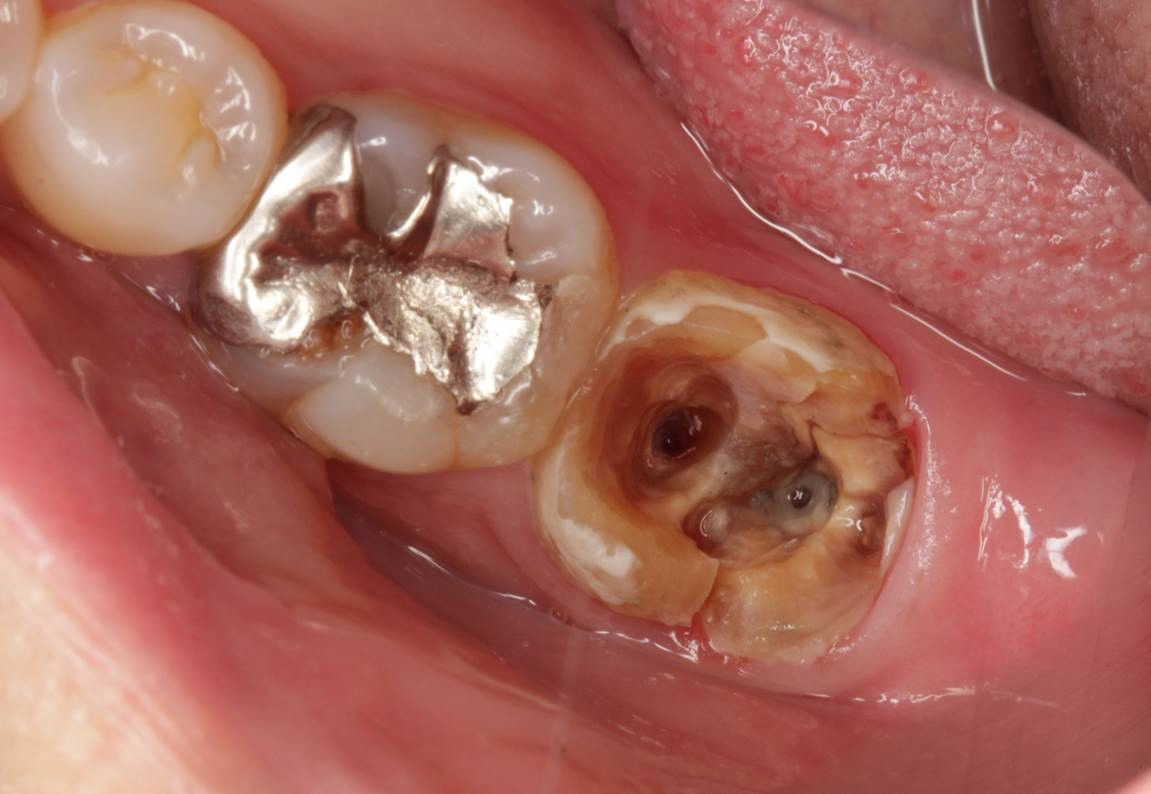

画像は、装着したばかりのクラウン周囲の歯茎が腫れて痛みが続いている患者様の相談でした。クラウンとメタルコア支台築造材料を撤去した状態の根の中の状態です。歯の中の髄床底と呼ばれる部分に破折線が見られ、「歯根縦破折に伴う急性根尖性歯周炎」の診断のもと、抜歯適応である旨を説明しました。